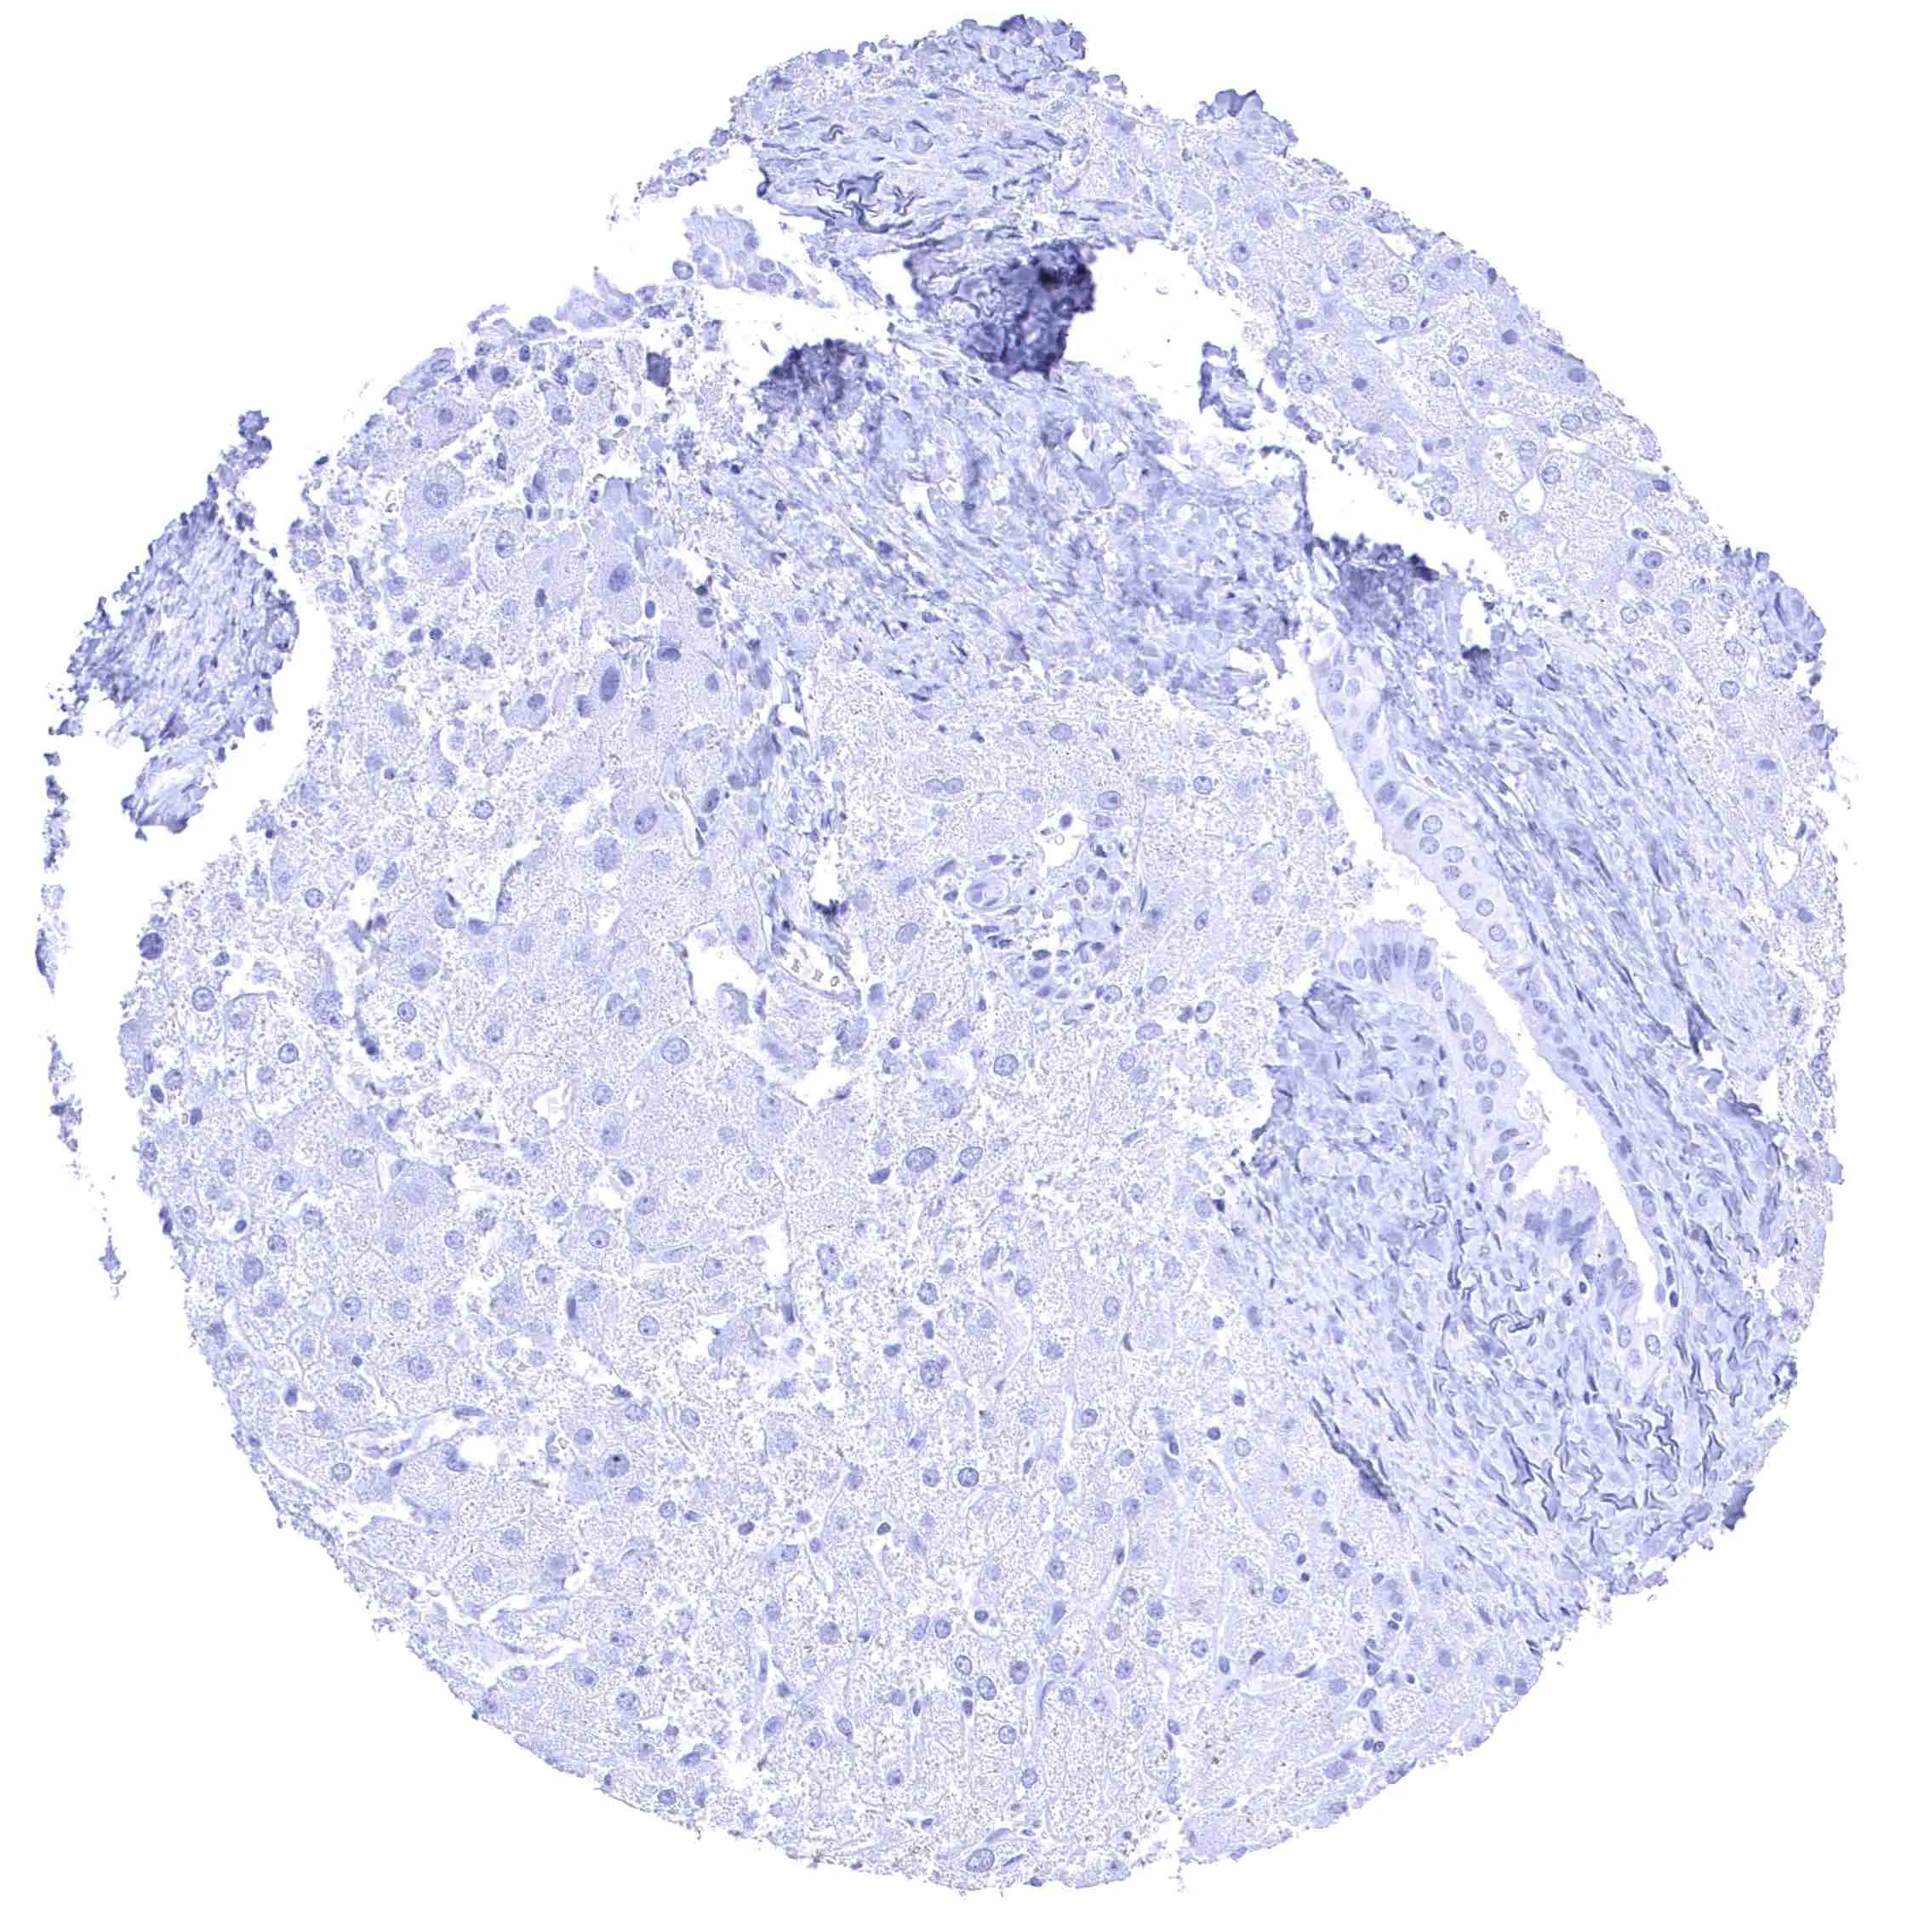

Liver